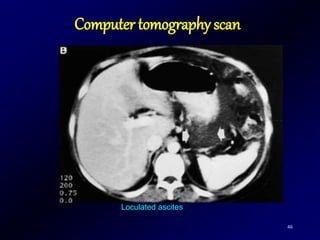

Computer tomography scan

46

Loculated ascites